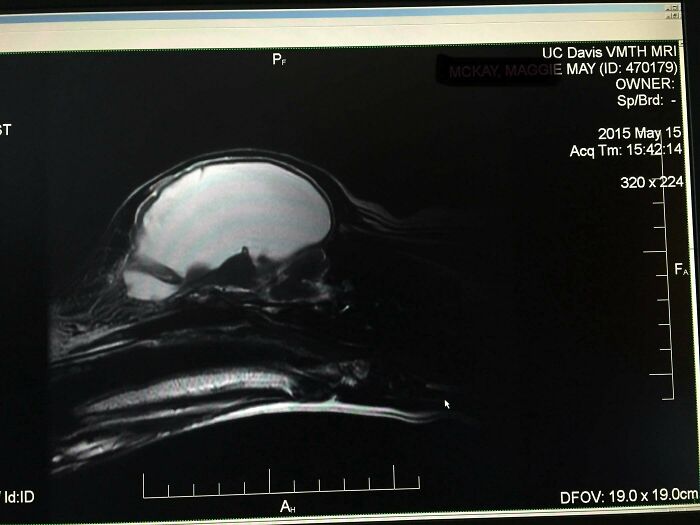

After Having A Dog For 6 Years, We Found Out She Had (Almost) No Brain

We’d had this dog 6 years, she’d had a litter of puppies, and lived a normal life (although we always noticed she was a little off). She had a seizure, so we took her to the vet. They ran labs and noticed her sodium was extremely low and kept her overnight. She was then sent to UC Davis where the vets were surprised she could walk based on her labs. After days of testing they did an MRI and discovered she had hydrocephalus and 95% of her brain cavity was fluid. All of the white you see in the MRI was fluid. Second picture is a comparison to a “normal” dog.

And her low sodium levels were her body’s way of keeping her brain in some form of homeostasis. They sent her home with instructions to provide lots of water and that was it. She lived until 12 when she started having regular seizures and we had to say goodbye.

Our weirdo medical miracle